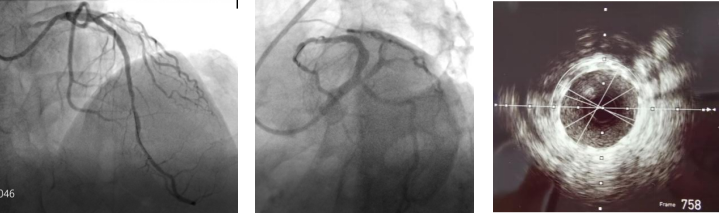

术后造影

在楚天舒主任指导下,团队顺利使用Shockwave IVL震波球囊对钙化病变处进行多个周期的冲击波治疗。治疗中可见冲击波球囊逐渐扩张开顽固钙化区域,冲击波治疗后复查造影可见左前降支近中段的钙化狭窄处明显改善。术中植入的2枚药物洗脱支架在行IVUS中可见支架贴壁和膨胀良好,血管扩张成形满意。术中患者无明显不适,未见低血压、ST改变及心律失常,术后患者胸痛症状明显好转。目前,该患者病情平稳,胸痛症状完全缓解。